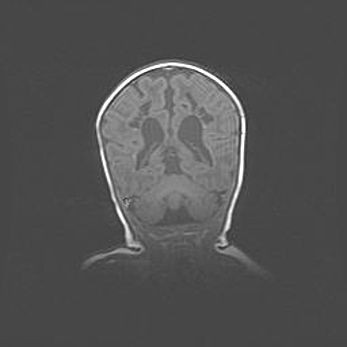

Наружная гидроцефалия с возможной атрофией височных областей.

Возраст: 28 дней

Вес: 3670 г

Пол: мужской

Окружность головы: 38 см

Срок гестации: 40 недель

Гидроцефалия головного мозга у новорожденных – это заболевание, которое характеризуется скоплением избыточного количества спинномозговой жидкости в желудочковой системе головного мозга в результате затруднения её перемещения от места выработки к месту поглощения в кровеносную систему или вследствие нарушения абсорбции. При открытой наружной форме гидроцефалии у новорожденных расширяются и переполняются субарахноидные пространства.

При нормотензивных  формах,  которые,  как  правило,  являются  следствием  перенесенных ишемических  повреждений  паренхимы  мозга,  возможно  сочетание микроцефалии  с нормотензивной гидроцефалией. В основе данных изменений лежит атрофия больших полушарий с преимущественной  локализацией  в  лобно-височных  областях.